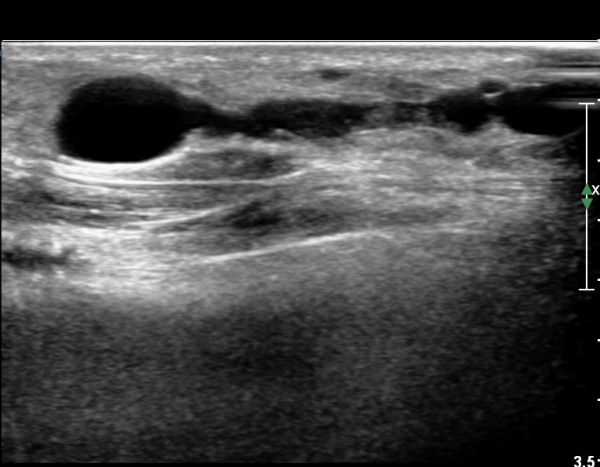

¾ÕÂÊ ¸»´Ü °æ°ñºñ°ñ°üÀý ¾à 5cm ±ÙÀ§ºÎ Ⱦ´Ü몀°Ë»ç ½Ã õºñ°ñ½Å°æ Àü¸é¿¡ Àú¿¡ÄÚ ³¶Á¾¿¡ ÀÇÇÑ ½Å°æ ¾Ð¹ÚÀÌ °üÂûµÈ´Ù(ÀÌ °üÂûµÈ´Ù(»çÁø 6, 7).